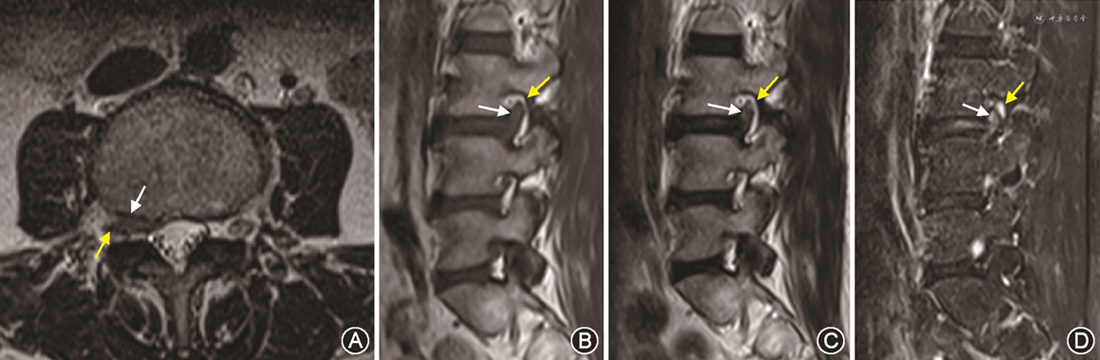

1. Lee系统:83例患者中,评估为0级的有21例,其中保守组17例,手术组4例,MRI表现为椎间孔无狭窄,椎间孔内神经根周围无脂肪闭塞(图2);评估为1级的有31例,其中保守组22例,手术组9例,MRI表现为椎间孔轻度狭窄,椎间孔内神经根周围脂肪有两个相对方向的闭塞,未看到神经根的形态学变化(图2, 3, 4);评估为2级的有11例,其中保守组3例,手术组8例,MRI表现为椎间孔中度狭窄,椎间孔内神经根周围脂肪有4个方向的闭塞,神经根无形态学变化(图3);评估为3级的有20例,其中保守组7例,手术组13例,MRI表现为椎间孔严重狭窄,出现神经根塌陷或形态学改变,部分显示欠清晰(表1)。

2. 改良系统:83例患者中,评估为0级的有3例,其中保守组3例,手术组无病例,MRI表现为椎间孔无狭窄,神经根周围无脂肪闭塞;评估为1级的有19例,其中保守组18例,手术组1例,MRI表现为椎间孔轻度狭窄,神经根无明显形态学改变,神经根周围脂肪闭塞小于神经根周长的50 %(图2);评估为2级者14例,其中保守组13例,手术组1例,MRI表现为椎间孔中度狭窄,神经根无明显形态学改变,神经根周围脂肪闭塞大于神经根周长的50 %;评估为3级者47例,其中保守组15例,手术组32例,MRI表现为椎间孔重度狭窄,清晰显示神经根被挤压在椎间孔上壁并明显变细或塌陷(图3、4,表1)。